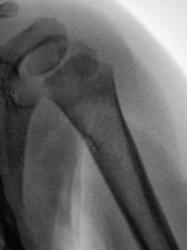

Направлен ребенок с подозрением "на перелом".

Мама с направлением хирурга явилась в рентген-кабинет. Диагноз - "перелом?".

Похоже на кортикальный дефект. Жалко, что нет второй проекции...

Очень может оказаться fibrous cortical defect; представить себе impressed cortical Fx в такой локализации весьма сложно.

не похоже на перелом, но хотелось бы узнать анамнез, клинику, увидеть вторую проекцию...

Травма была. Ребенок вывалился из кровати, по ургенту сделали одну проекцию. Второй проекции просто нет - её делали (2 раза), но из-за беспокойства ребенка анализу снимки не подлежат. Родители со снимком, произведенным в прямой проекции поехали в областной центр к детскому ортопеду.

здесь нет перелома